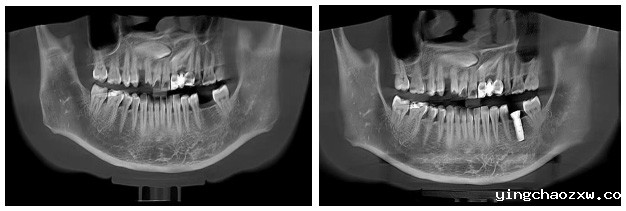

据悉,患者1年前因龋坏拔除左下后牙1颗,但未进行修复。今年2月,因咀嚼效率不佳到新利官网登录北院区(新平县人民医院)口腔科就诊。为帮助患者修复缺失牙齿,提升患者生活质量,昆明医科大学附属口腔医院对口帮扶专家、主治医师张云鹏博士带领北院区口腔科医疗团队对患者缺失牙齿部位进行了全面细致的检查,并为其制定了种植修复方案。在长达2个多月的筹备工作中,新利官网登录先后引进种植牙机、口腔CT等先进诊疗设备,为种植牙技术的顺利开展提供了坚实的硬件支撑,并于6月4日为患者开展种植牙一期手术。术中微创操作,患者完全无痛,术后无不良反应,整个诊疗过程舒适、安全、精准。经术后影像检查,种植体植入位置良好,手术获得圆满成功,患者及家属对本次治疗效果非常满意。